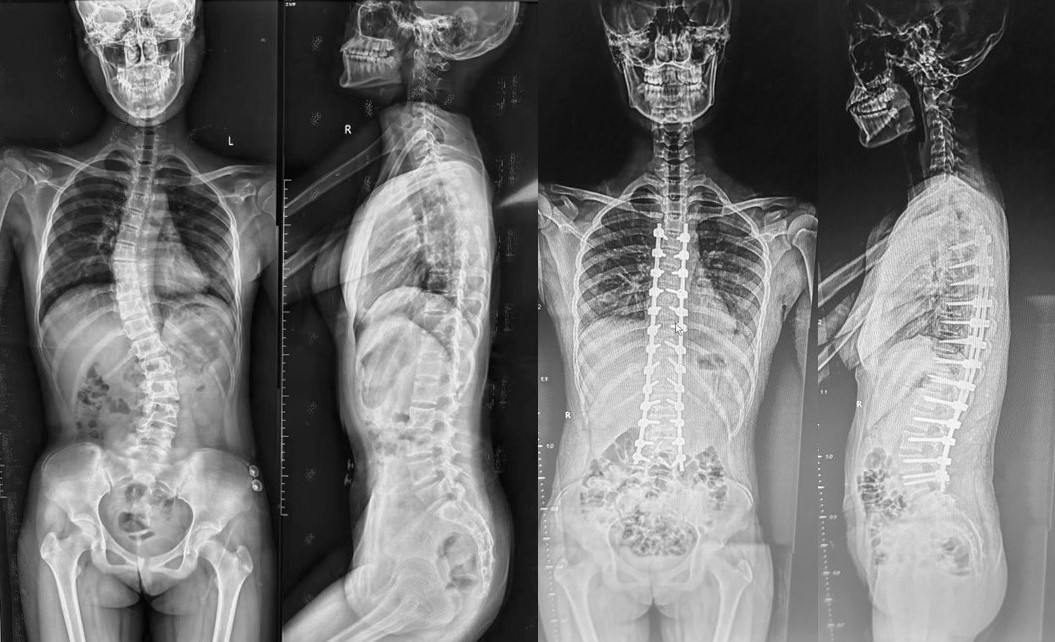

病例3是一名15岁的青少年特发性脊柱侧弯患者,由于保守治疗无效,侧弯度数逐渐增大,严重影响日常生活。经专家团队仔细阅片和详细测量后确定为临床上较为少见的LENKE6型脊柱侧弯,同时制定了详细的手术方案,由李浩鹏主任、蔡璇副主任及王瑞主治医师成功为患者实施了脊柱畸形矫正术,获得了教科书般的矫正效果,畸形矫正率近100%。术后患者家属激动表示感谢治疗团队让其孩子重获挺拔人生(图3)。

病例3:青少年特发性脊柱侧弯,行脊柱非选择性固定融合术